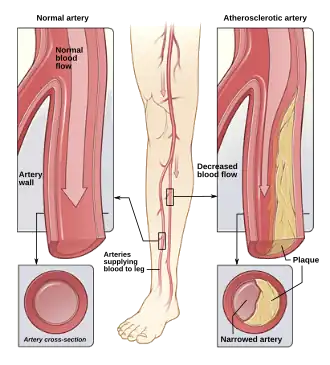

Peripheral artery disease PAD is the abnormal narrowing of the arteries which supply the limbs. Patients with this condition can present with intermittent claudication which is pain mainly in the calves and thighs while walking. If there is progression, a patient may also present with chronic limb threatening ischemia which encompasses pain at rest and non-healing wounds. Vascular surgeons are experts in the diagnosis, medical management, endovascular and open surgical treatment of PAD.[20]

A vascular surgeon may diagnose PAD using a combination of history, physical exam and medical imaging. Medical imaging may include ankle-brachial index, doppler ultrasonography and computed tomography angiography, among others. Treatments are individualized and may include medical therapy, endovascular intervention or open surgical options including angioplasty, stenting, atherectomy, endarterectomy and vascular bypass, among others.

Illustration of atherosclerosis causing arterial obstruction which clinically presents at peripheral artery disease.

Illustration of atherosclerosis causing arterial obstruction which clinically presents at peripheral artery disease. -